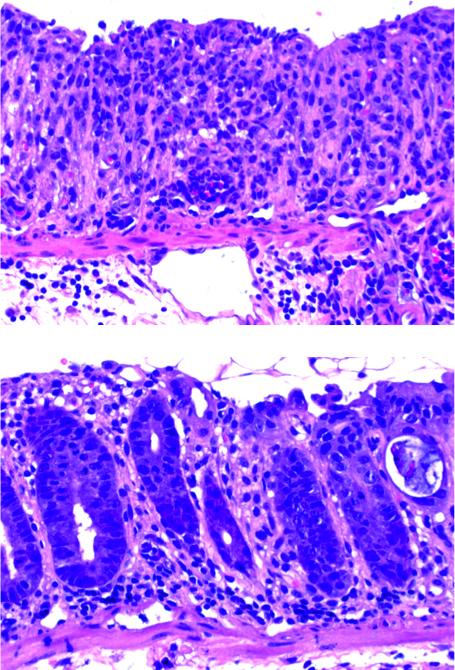

The gut mucosa is not only responsible for the uptake of nutrients, but it also forms a barrier against the microbes that inhabit our intestine. If this barrier is broken, inflammation of the gut, colitis, develops. Upper graph (wildtype): By inducing experimental colitis, the mucosa structure is destroyed and a large infiltrate of inflammatory cells is present. Lower graph: Organisms lacking transcription factor IRF9 are more resistant, seen by a more intact crypt structure and less inflammatory cells.